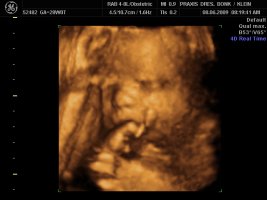

Und dann haben wir endlich unser Video gemacht, Zeit hatten wir ja nun genug und das ist voll süß geworden, sie war wohl auch wie Mama müde, denn sie hatte öfter mal gegähnt und mit den Augen geblinzelt :love1 ...kann es kaum noch erwarten die Kleine in die Arme zu nehmen :applaus

Und wir haben endlich ein Beweisfoto bekommen, dass es ein Mädchen ist...

Hier ein paar Bilder von Montag, neben dem Video haben wir auch sehr viele Bilder mitbekommen.... :love1

Anhänge

• Bild 1.jpg

Bild 1.jpg

72,4 KB · Aufrufe: 72

• Bild2.jpg

Bild2.jpg

75,1 KB · Aufrufe: 72

• Bild3.jpg

Bild3.jpg

61,5 KB · Aufrufe: 72

@Imke ui was für schöne Bilder, will auch! *jammer*